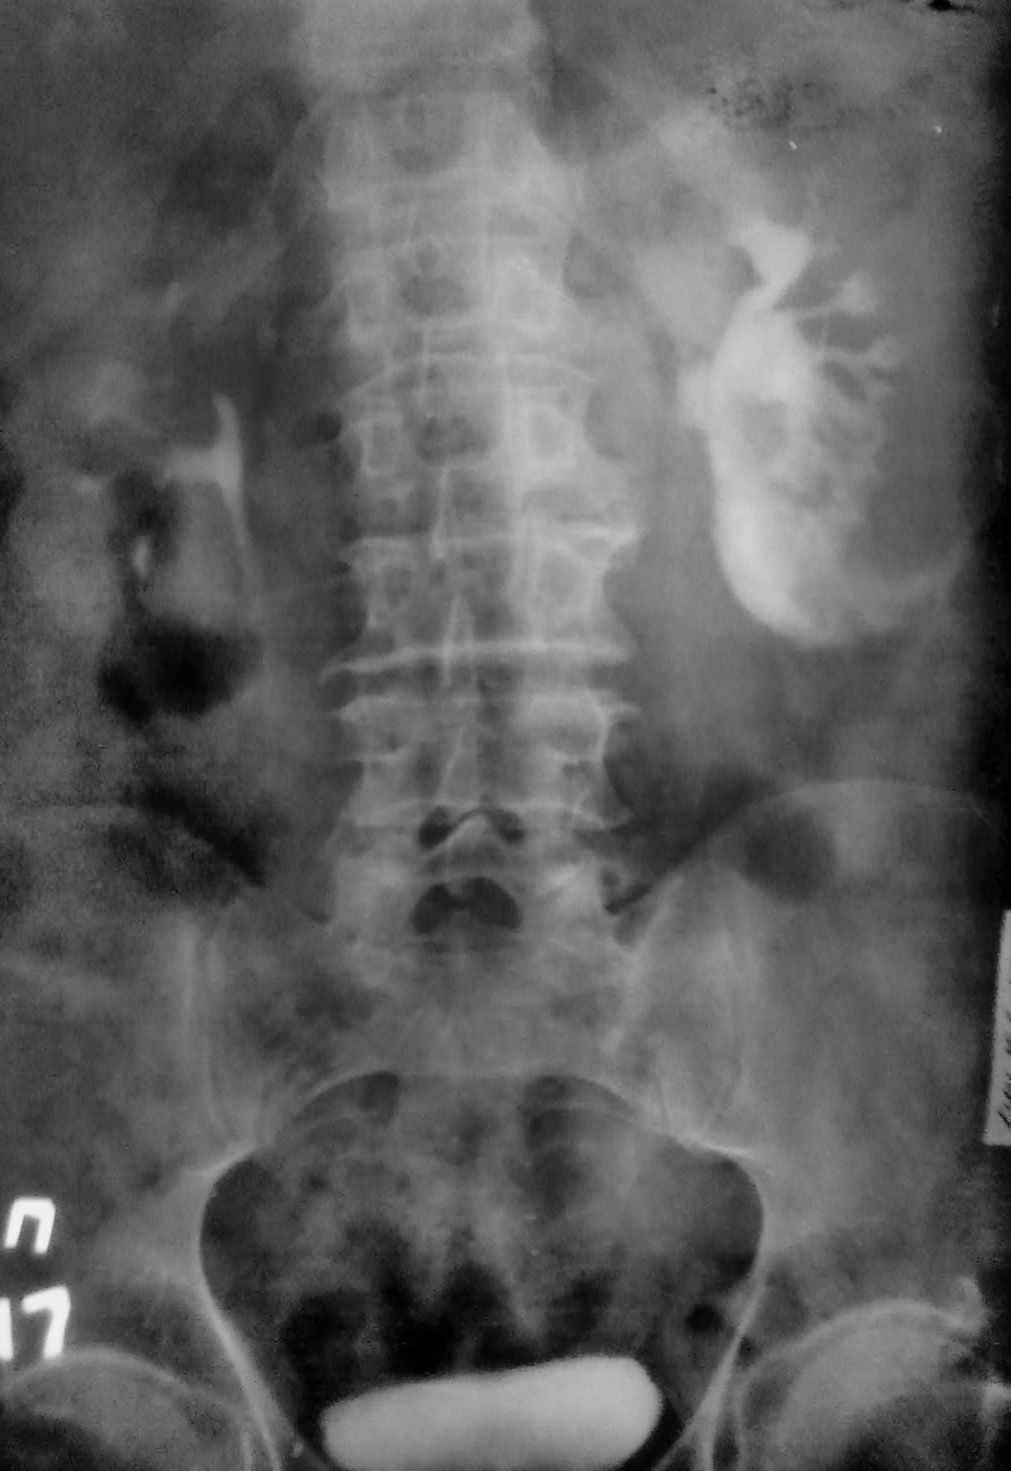

Представляю Вам в\в урографию без коментариев. Случай классический.

Разрыв почки? Затек контраста?

Все правильно, это тоже криминальная травма, сукапсулярный и капсулярный разрыв нижнего полюса левой почки и затек контраста паранефрально...

Спасибо за "рихтовку" снимков, просто хотелось показать как выглядит затек в паренхиму, под капсулу и вне капсулы...в этом плане случай очень показателен. Кстати, больного не оперировали, заживление, он жив и, как видите, судится с обидчиками....